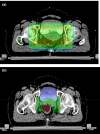

Figures